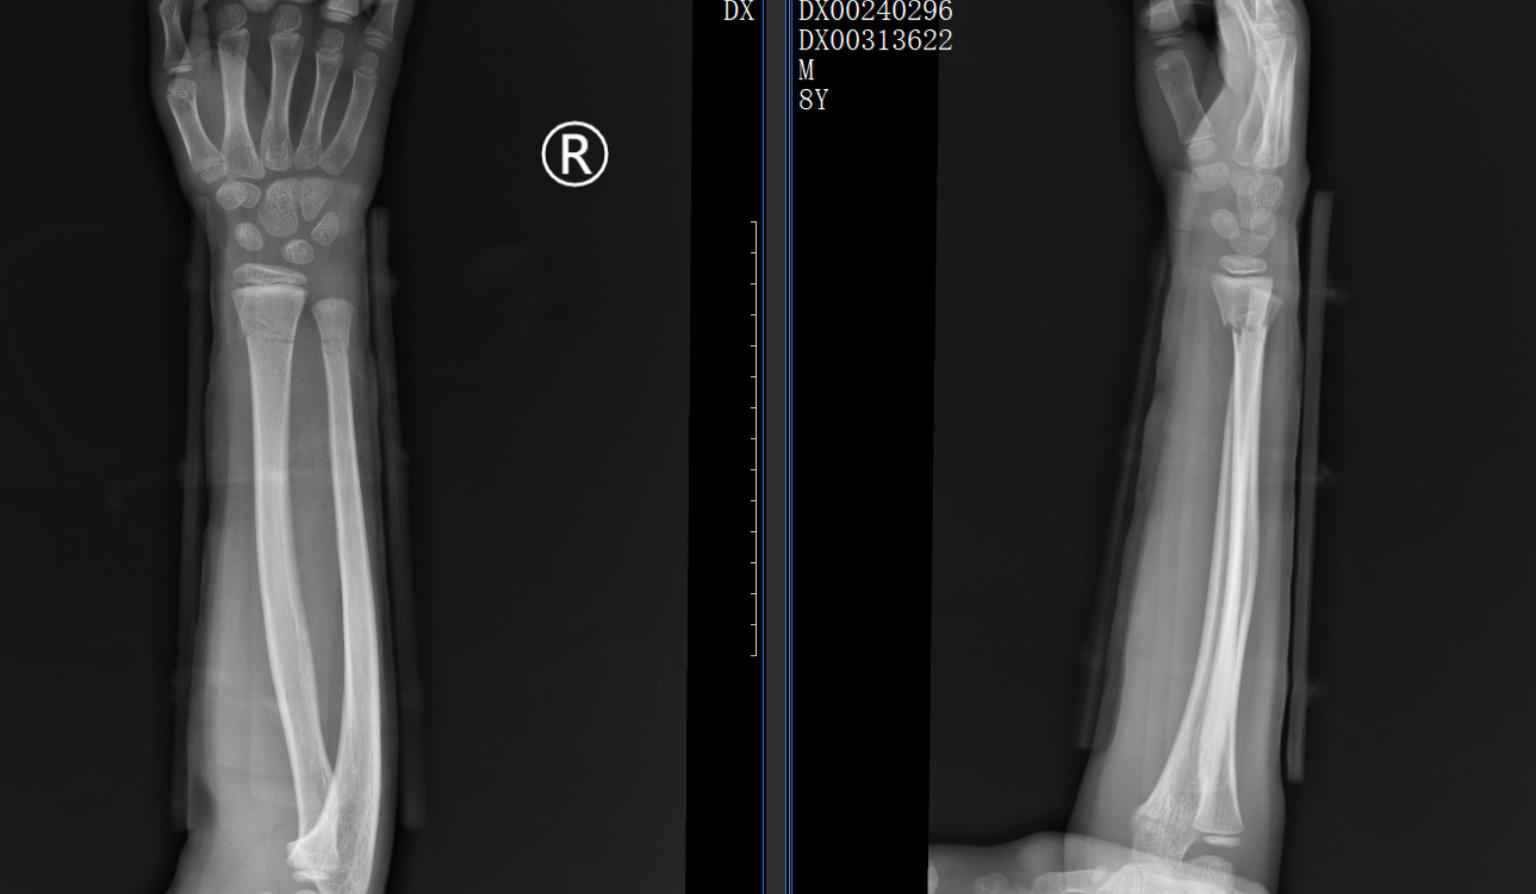

一位 8歲的學(xué)生在上學(xué)途中不慎摔傷,造成尺橈骨遠(yuǎn)端骨折。家屬心急如焚,為保守治療來到了我院中醫(yī)正骨中心就診。中醫(yī)正骨醫(yī)師運(yùn)用精湛的手法為小朋友進(jìn)行了復(fù)位,并配合夾板固定。3 周后骨痂形成,小朋友的功能活動(dòng)也恢復(fù)良好。這一案例,讓家其屬深刻體會到了中醫(yī)正骨的獨(dú)特魅力。

正骨前后影像資料